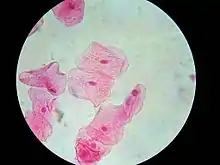

Biopsy

Tissue biopsy is usually indicated[5] to rule out other causes of white patches and also to enable a detailed histologic examination to grade the presence of any epithelial dysplasia. This is an indicator of malignant potential and usually determines the management and recall interval. The sites of a leukoplakia lesion that are preferentially biopsied are the areas that show induration (hardening) and erythroplasia (redness), and erosive or ulcerated areas. These areas are more likely to show any dysplasia than homogeneous white areas.[5]

Brush biopsy/exfoliative cytology is an alternative to incisional biopsy,[5] where a stiff brush is scraped against the lining of the mouth to remove a sample of cells. This is then made into a smear which can be examined microscopically. Sometimes the biopsy site can be selected with adjunct methods which aim to highlight areas of dysplasia. Toluidine blue staining, where the dye is preferentially retained by dysplastic tissue, is sometimes used, but there is high false positive rate.[3] Other methods involve the use of luminescence, relying on either the property of normal autoflorescent molecules in mucosa such as collagen and keratin which is lost from areas of dysplasia or carcinoma under blue light or by initially staining of the mucosa with toluidine blue or dilute acetic acid and examination under white light.[3]

Histologic appearance

Leukoplakia has a wide range of possible histologic appearances. The degree of hyperkeratosis, epithelial thickness (acanthosis/atrophy), dysplasia and inflammatory cell infiltration in the underlying lamina propria are variable.[29] In mucous membranes, hyperkeratosis can be defined as "an increase in the thickness of the keratin layer of the epithelium, or the presence of such a layer in a site where none would normally be expected."[22] In leukoplakia, the hyperkeratosis varies in thickness and may be either ortho- or para-keratosis, (depending upon whether cell nuclei are lost or retained in the superficial layers respectively), or a mixture of both in different areas of the lesion.[29][38]

The epithelium may show hypertrophy (e.g. acanthosis) or atrophy. Red areas within leukoplakia represent atrophic or immature epithelium which has lost the ability to keratinize.[1] The transition between the lesion and normal surrounding mucosa may be well-demarcated, or poorly defined. Melanin, a pigment naturally produced in oral mucosa, can leak from cells and give a grey color to some leukoplakia lesions.[29]

Hyperkeratosis and altered epithelial thickness may be the only histologic features of a leukoplakia lesion, but some show dysplasia. The word "dysplasia" generally means "abnormal growth", and specifically, in the context of oral red or white lesions, refers to microscopic changes ("cellular atypia") in the mucosa that indicate a risk of malignant transformation.[3] When dysplasia is present, there is generally an inflammatory cell infiltration in the lamina propria.[38] The following are commonly cited as being possible features of epithelial dysplasia in leukoplakia specimens:[3][29]

- Cellular pleomorphism, in which cells are of abnormal and different shapes.

- Nuclear atypia, in which the nuclei of cells varies in size, any may be increased in size relative to the cytoplasm, shape, and may stain more intensely. There may also be more prominent nucleoli.

- Increased number of cells seen undergoing mitosis, including both normal and abnormal mitoses. Abnormal mitosis may be abnormally located, e.g. occurring in suprabasal cells (cell layers more superficial to the basal cell layer) or of abnormal form, e.g. "tri-radiate mitoses" (a cell splitting into 3 daughter cells rather than only 2)

- Loss the normal organization of the epithelial layers. The distinction between the epithelial layers may be lost. Normally stratified squamous epithelium shows progressive changes in the form of cells from the basal to the superficial layers, with cells becoming more flat ("squames") towards the surface as a continuous maturation process. In dysplastic epithelium, cells may become vertically orientated rather than becoming flat towards the surface.

- There may be abnormal keratinization, where keratin is formed below the normal keratin layer. This can occur in individual cells or groups of cells, forming an intraepithelial keratin pearl. There may be an increase in the number of basal cells, and they may lose their cellular orientation (losing their polarity and long axis).

- Alteration of the normal epithelial-connective tissue architecture - the rete pegs may become "drop shaped". wider at their base than more superficially.

Generally, dysplasia is subjectively graded by pathologists into mild, moderate or severe dysplasia. This requires experience as it is a difficult skill to learn. It has been shown that there is high degree of inter-observer variation and poor reproducibility in how dysplasia is graded.[39] Severe dysplasia is synonymous with the term carcinoma in situ, denoting the presence of neoplastic cells which have not yet penetrated the basement membrane and invaded other tissues.